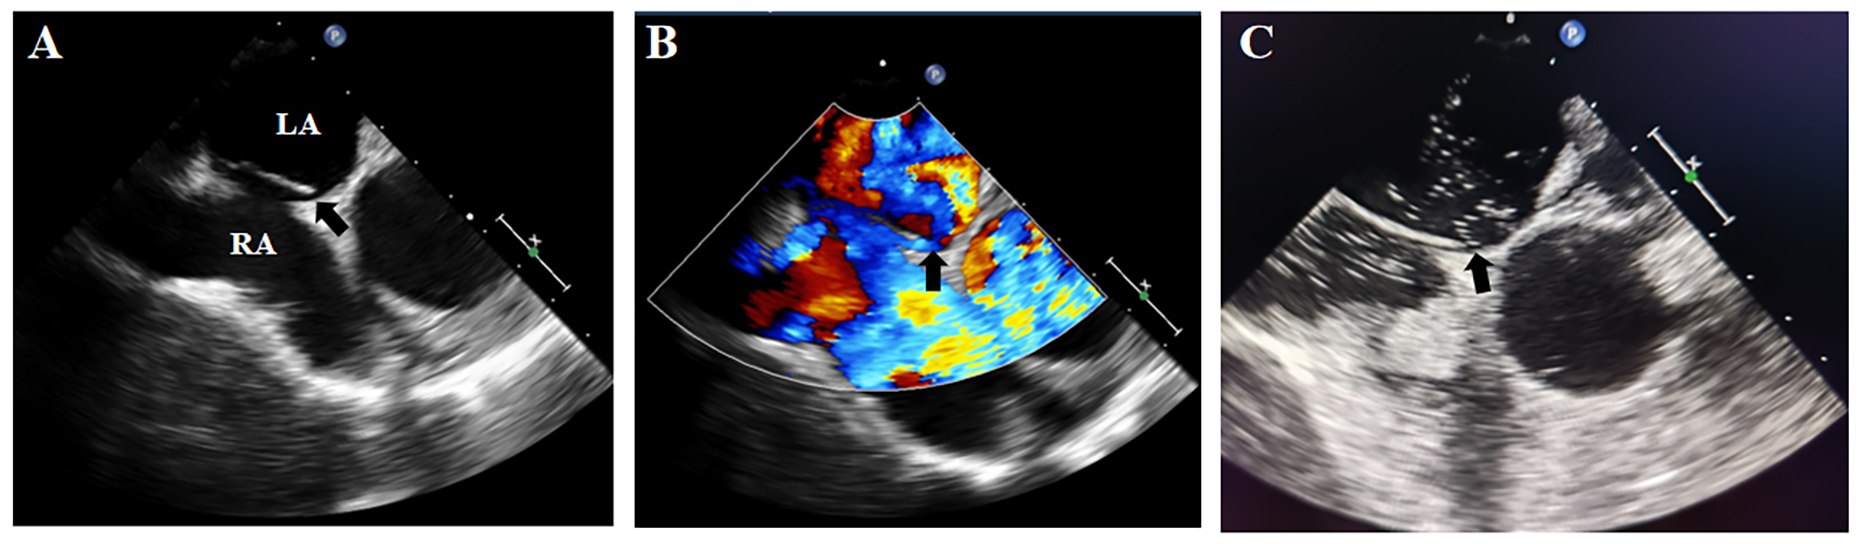

On postoperative day 3, early morning, the patient developed agitation and right-sided limb weakness with a positive Babinski sign on the right. Further brain CT demonstrated hypodense lesions indicating large-territory cerebral infarction in the left hemisphere (Figure 1C). Given the sequential occurrence of pulmonary embolism and cerebral infarction, the treating physicians clinically suspected a pathological right-to-left shunt pathway, such as arteriovenous fistula or PFO. TEE and bubble study was performed, revealing: Patent foramen ovale with significant right-to-left shunt (Figures 2A,B). Strongly positive bubble study (Figure 2C). The final diagnosis was PFO, pulmonary embolism and cerebral infarction.

Figure 2

Transesophageal echocardiographic findings. (A,B) Demonstrated a significant PFO with right-to-left shunting; (C): strongly positive bubble study. Black arrow: PFO. LA, left atrium; RA, right atrium.